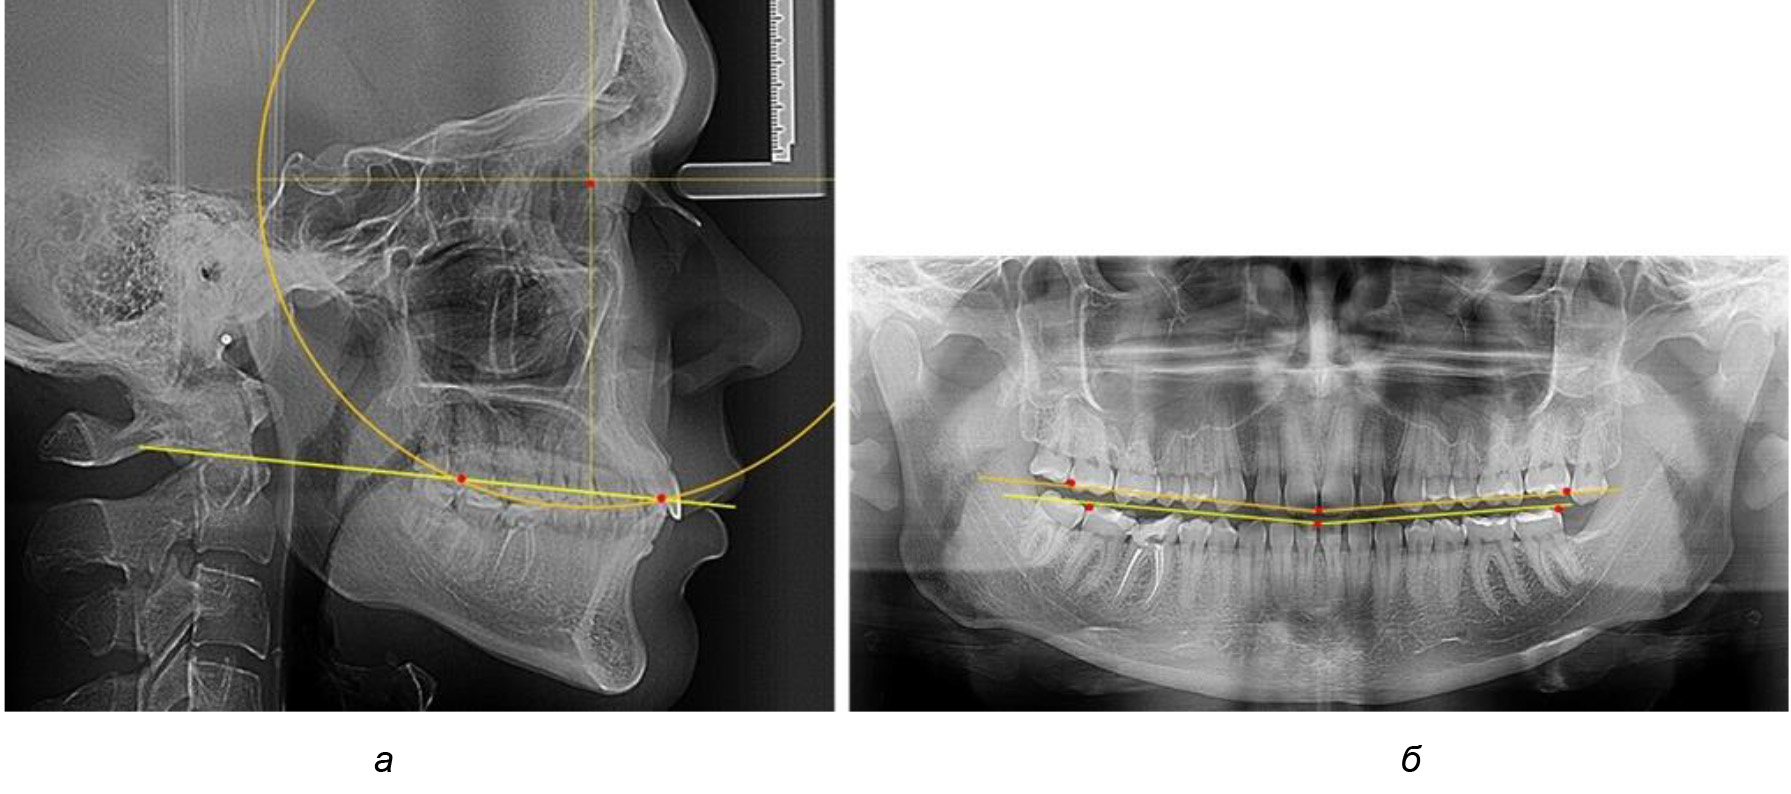

Во 2-й подгруппе 2-й группы было обследовано 7 человек.

Обращает на себя внимание, что глубина кривой Spee в анализируемой подгруппе практически не отличалась от показателей, полученных у людей с физиологической окклюзией, и составляла (4,23 ± 1,58) мм. Отношение радиуса окружности к сагиттальному размеру окклюзионной линии в среднем по подгруппе составляло 1,623 ± 0,02 и соответствовало числу Фибоначчи.

После лечения пациентов техникой «прямой» дуги, так же как и в 1-й подгруппе, было отмечено увеличение сагиттального размера окклюзионной лини в среднем на (2,38 ± 0,83) мм. Окклюзионная линия практически касалась окклюзионного контура всех жевательных зубов, и отмечалось практически полное отсутствие кривой Spee, так же как и у людей 1-й подгруппы 2-й группы (рис. 6).

Рис. 6. Особенности ТРГ при оптимальной кривой Spee до лечения (а) и после лечения (б) техникой «прямой» дуги

Таким образом, проведенное лечение техникой «прямой» дуги способствует нормализации окклюзионного равновесия и торку передних зубов, однако не соответствует оптимальному окклюзионному статусу, характеризующему физиологическую окклюзию. При этом величина нижнечелюстного угла оставалась на прежнем уровне.